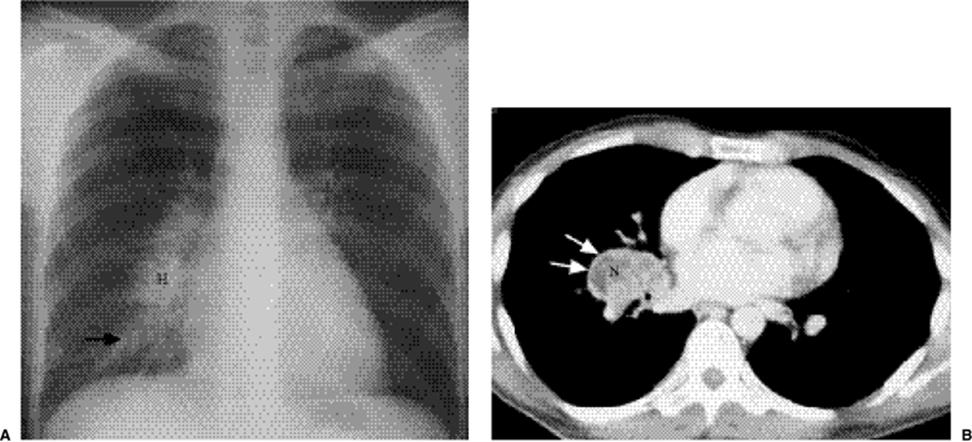

Figure 5.38 Atypical appearance of nontuberculous mycobacteria. A. Posteroanterior chest x-ray: large right hilum (H) with adjacent right lower lung airspace disease (arrow). (B) Computed tomography: enlarged low attenuation right hilar lymph node (N) with enhancing rim (arrows).